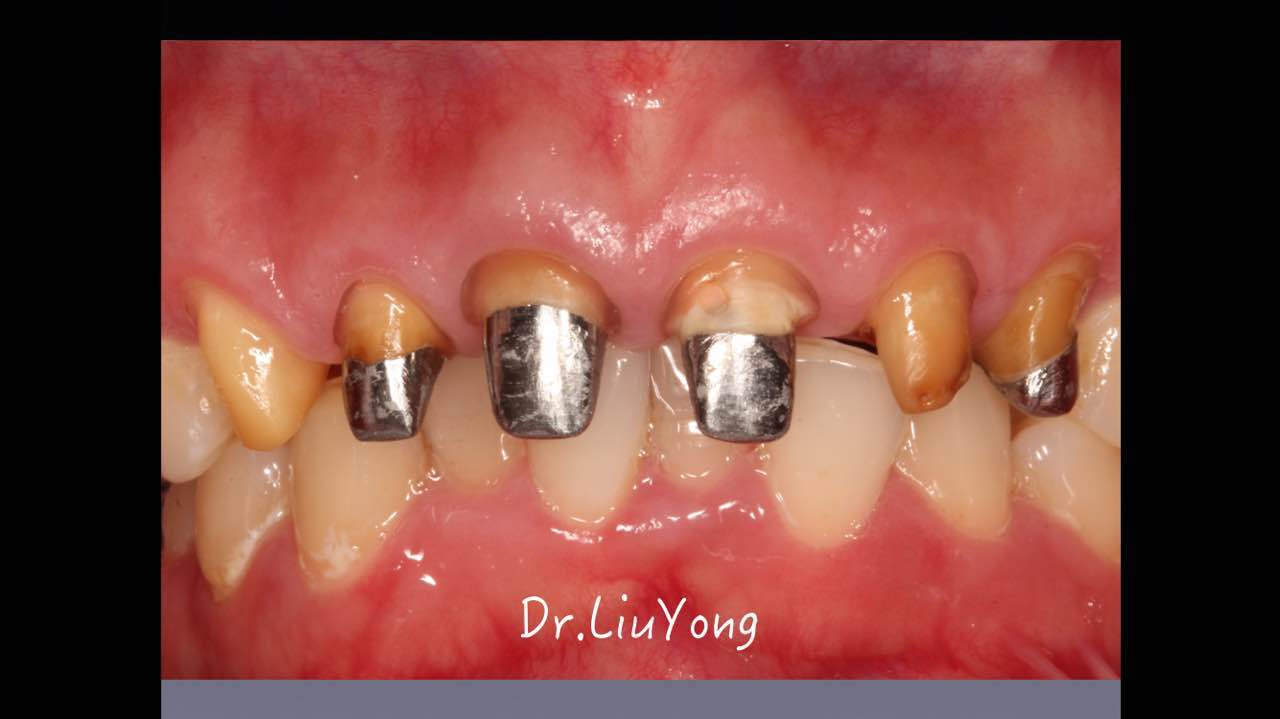

嚴重破壞生物學寬度,根尖瘺管,重行根管治療, 第一次冠延長建立唇腭側(cè)及鄰面BW,術后牙齦扇貝形差, 齦乳頭黑三角,再次行美學冠延長,建立牙齦扇貝形,手術免費, 患者因經(jīng)濟原因只能選擇鑄樁及鈷鉻合金烤瓷冠。終于完工